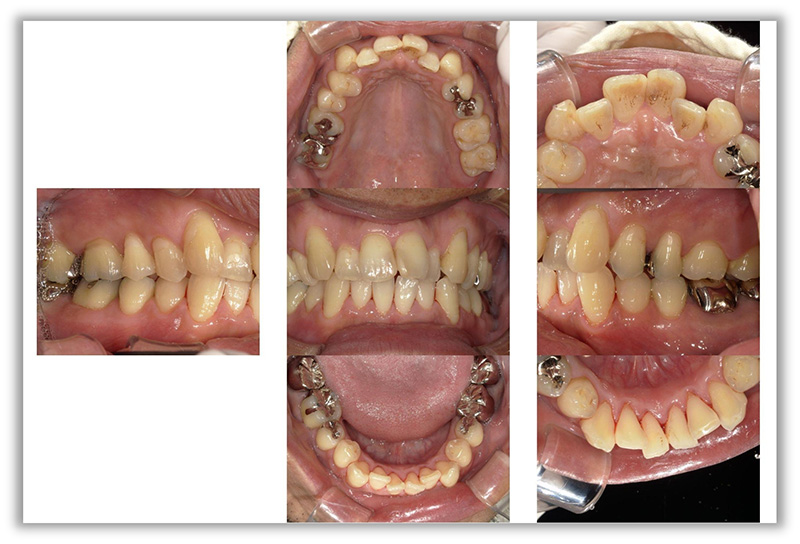

CASE_04

50代女性(インビザライン矯正+セラミック治療)

- 患者さん情報(年齢・性別)

- 50代 女性

- 主訴

- 歯並びが気になる、被せものがとれている

- 治療箇所

- インビザライン、セラミック4か所

- 治療方法

- インビザライン、セラミック治療

- 費用

- インビザライン66万円、セラミック治療22万円

- 治療期間

- 約4年

- その治療によるリスク・副作用

- 保険が効かない

- 歯肉退縮することがある

- 矯正中はしみたり、痛みを伴うことがある

- 患者様の声